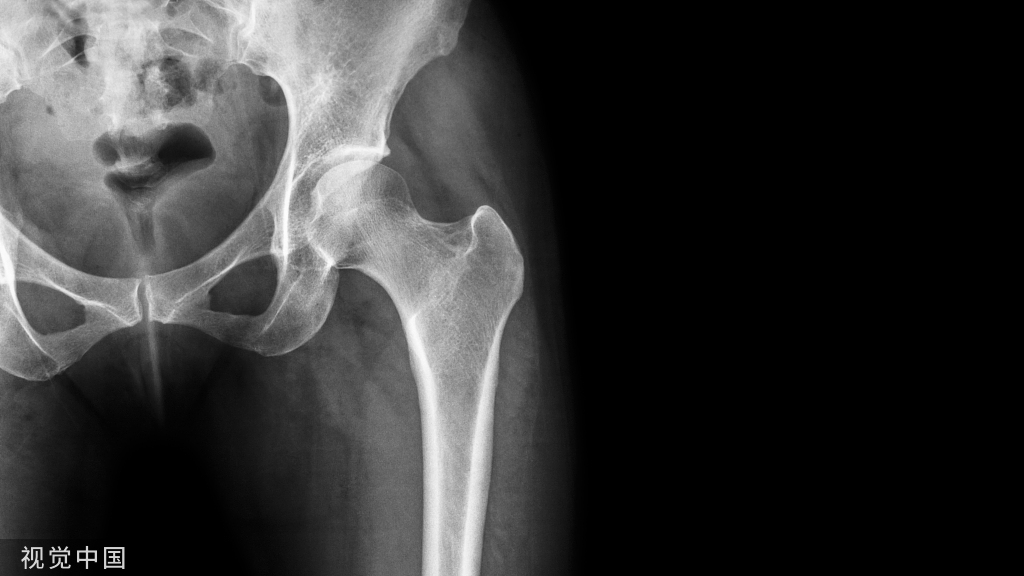

ACL的解剖特点

1、ACL起于胫骨髁间棘前方稍偏内侧,斜向后上止于股骨外髁髁间侧面后部;长约15-20mm(胫骨后推)

2、胫骨端附着部较粗大,呈卵圆形,面积约3平方厘米。

3、股骨附着部相对细小,呈扇形,面积约2平方厘米。

ACL三束:前内束屈膝时紧张;后外束伸膝时紧张;中间束在膝关节屈伸运动中始终保持张力。

正常ACL与胫骨平台保持一定的角度,屈膝90度时约30度,伸直时为40~45度。